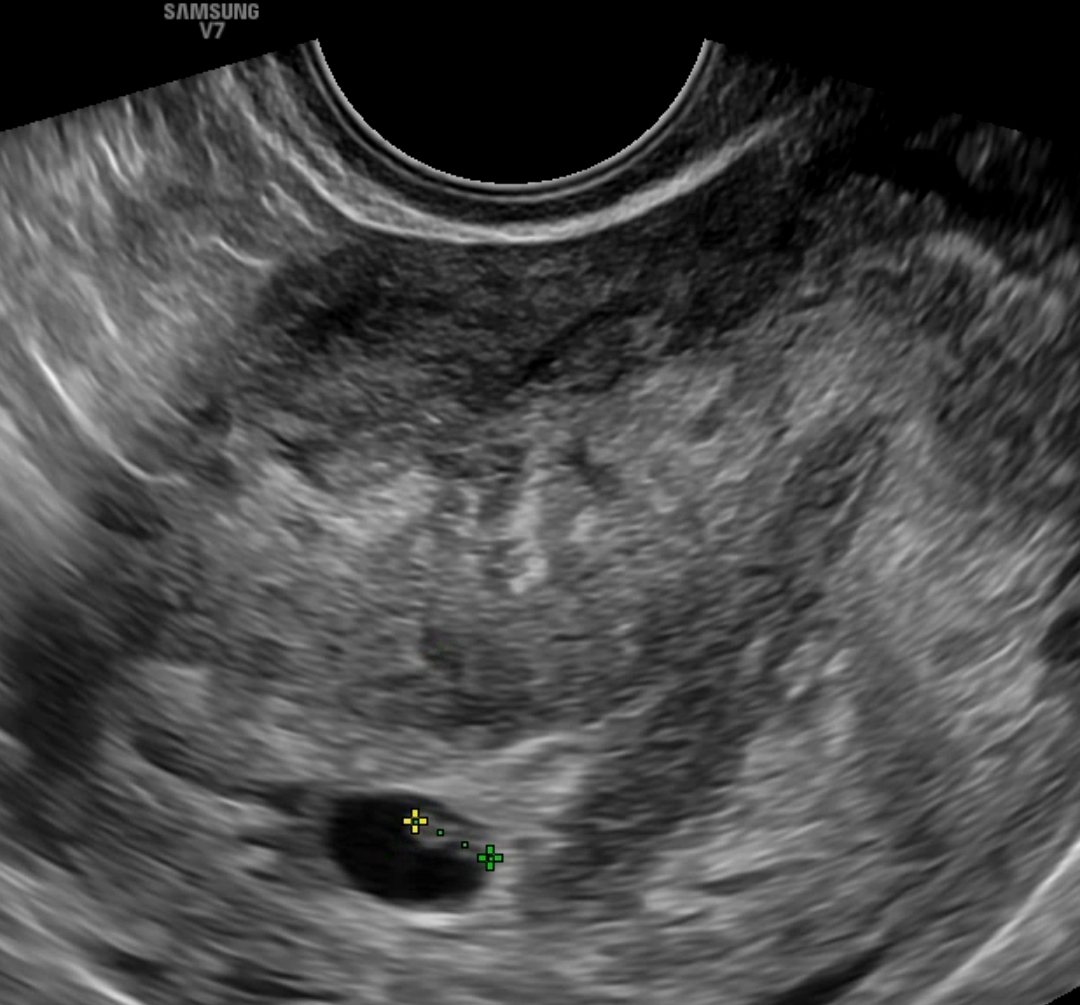

시험관주수 6주 4일 / 예상주수 6주1일 심장박동 확인

📍심장박동은 111bpm이 찍혔다.

아기는 이틀사이에 0.29 -> 0.46 로 조금 컸다 ㅠㅠ

✔️주수에 비해 3일정도 느리다고 하셨다 계속 3일씩 밀리니까 뭔가 불안한마음...